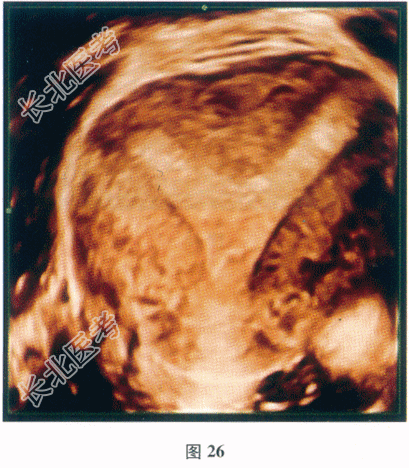

- 多项选择题2.【提示】超声检查情况见图26。

目前考虑患者的诊断是( ) A、双角子宫

C、子宫完全纵隔

E、子宫不全纵隔

F、弓形子宫